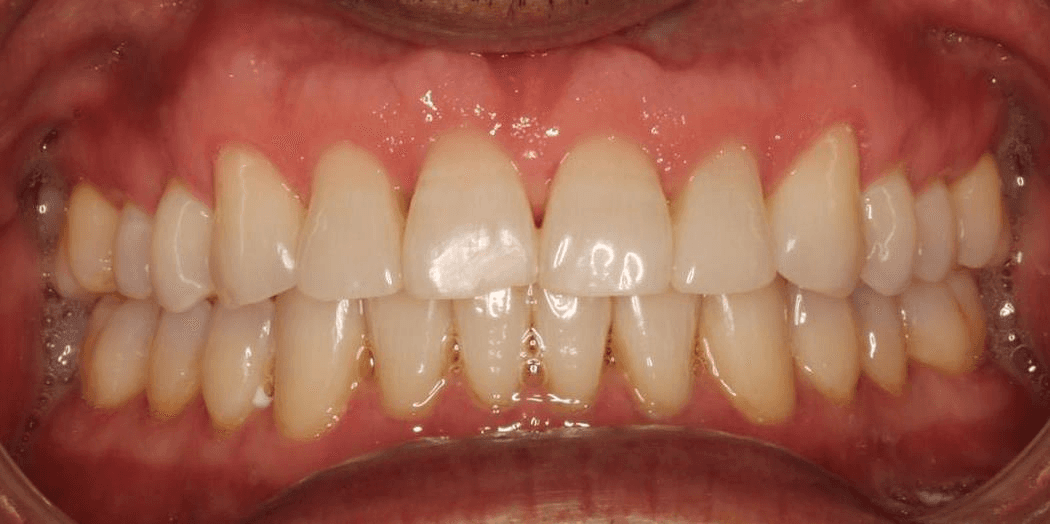

INTRAORAL